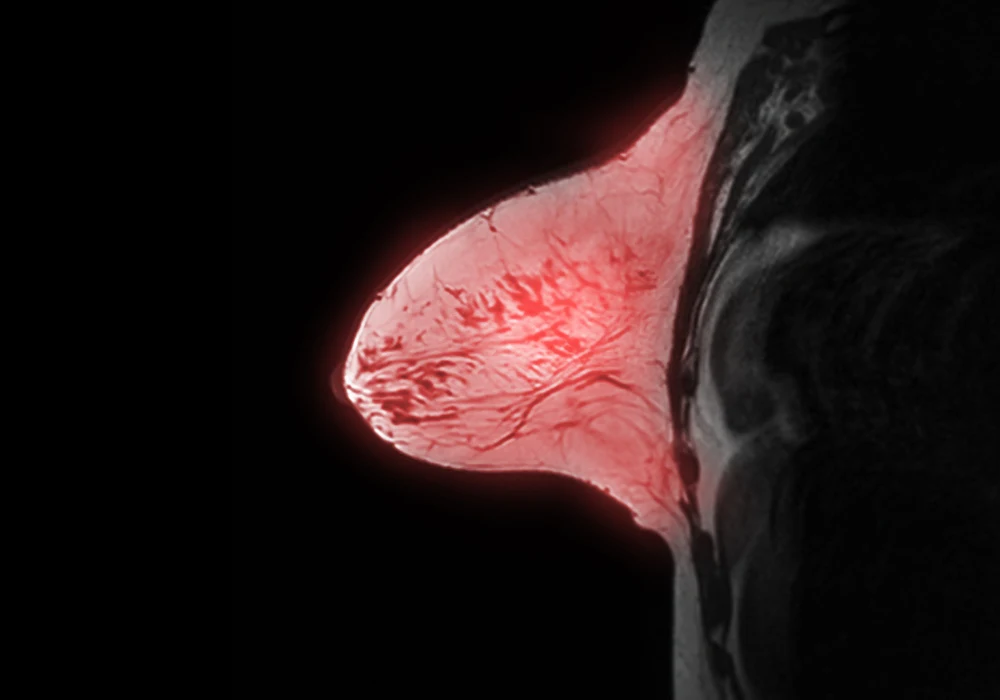

Anomaly detection offers a different approach by focusing on learning the characteristics of normal breast MRI scans, enabling better identification of abnormalities even when malignant cases are scarce. The FCDD model applies this principle to dynamic contrast-enhanced MRI data, generating pixel-level anomaly scores that can be aggregated into breast-level predictions. This method avoids reliance on secondary interpretability techniques and does not require lesion annotations, allowing for more direct and robust heat maps of suspected malignancy.

Across both balanced and imbalanced detection tasks, FCDD consistently outperformed BCE in AUC and AUPR, while HSC showed similar performance to FCDD in some scenarios. At operating points prioritising high sensitivity, FCDD achieved higher specificity, indicating a capacity to reduce false positives. In the imbalanced detection setting, its PPV was double that of BCE. Heat maps generated by FCDD exhibited significantly greater alignment with radiologist annotations than those from comparison models, suggesting stronger localisation of suspicious areas.

The model demonstrated generalisability, maintaining strong performance on the external multicentre dataset without retraining. Balanced detection AUC reached 0.86, surpassing both HSC and BCE. Explanation maps showed superior spatial accuracy and specificity, supporting their potential use in assisting radiologists during interpretation. Although pixelwise performance was lower for nonmass enhancements and in situ cancers—likely due to their subtler imaging features—FCDD performed well across most lesion types and stages.

By reducing false positives and offering interpretable outputs, the model could serve as a triage tool, rapidly excluding normal scans and directing radiologist attention to regions of concern. This capability may improve efficiency, particularly in screening programmes where the majority of cases are normal. The heat maps also act as a form of visual validation, helping radiologists assess the reliability of AI suggestions.